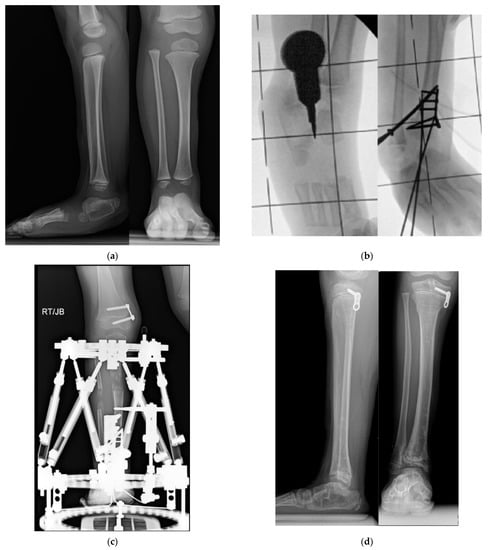

Figure 7.

(a) AP and lateral radiographs of 18-month-old girl with Paley type 3b1 FH. She has a rocker bottom foot and obvious subtalar coalition malunion. (b) Intraoperative fluoroscopic views showing splitting of subtalar coalition with an osteotome (left) and after shortening of tibia relative to fibula with plate fixation (SHORDT) combined with subtalar coalition malunion reduction and pinning. (c) Radiograph showing lengthening of tibia with computer dependent external fixator at the same surgery as the SUPERankle procedure. A hemiepiphysiodesis plate was also placed to treat the distal femoral valgus. (d) Final radiographs after removal of external fixator and after correction of proximal tibial valgus with a hemiepiphysiodesis plate. Note the stable appearance of the ankle joint and the plantigrade foot position. (e) Radiographic sequence of extramedullary lengthening with medially placed Precice nail (Nuvasive Specialized Orthopedics, California) (left). There is a Simple Locking IntraMedullary (SLIM) rod (Pega Medical, Montreal, Canada) and the fibula is fixed with tibio-fibular screws. The foot is fixed with a temporary extra-articular spanning screw from the foot to the tibia anterior to the ankle joint. A 5 cm lengthening was performed causing axial deviation into valgus bending the SLIM rod (middle). To correct the valgus, a plate was inserted laterally, and the extramedullary nail removed, after first decompressing the peroneal nerve, performing an anterior compartment fasciotomy and cutting the fibula proximally (right).